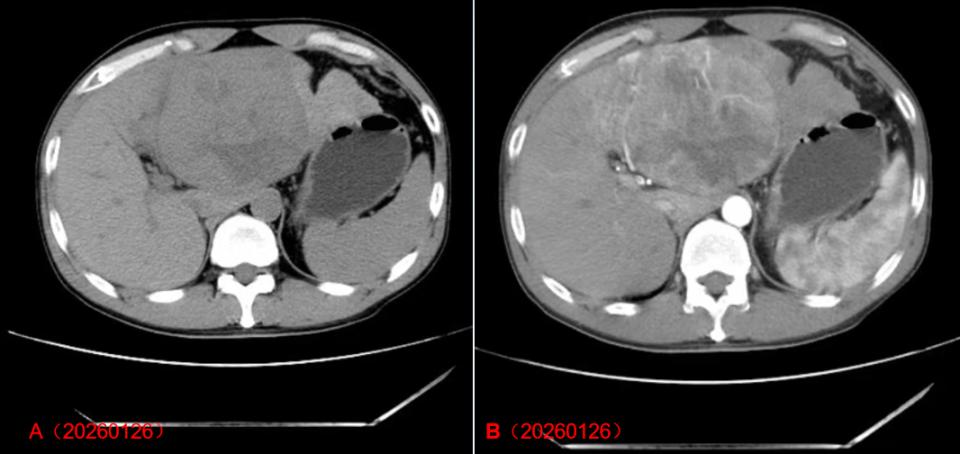

2026年1月23日于外院查上腹部CT平扫检查,显示肝左叶占位(97×90 mm)。两天后突然出现腹痛加剧且不能缓解,来我院急诊,我院以“腹痛待查”收治入院。入院后查房见痛苦面容,板状腹。2026年1月26日查凝血酶原活动度(PTA)83%,HBsAg 1370 IU/mL,ALT 52 IU/mL,AFP 678.4 ng/mL,甲胎蛋白异质体(AFP-L3)4.8%,APT 11991 mAU/mL。2026年1月26日CT增强显示肝左叶占位(95×110 mm),考虑肿瘤,并提示破裂出血可能。

HCC患者入院时CT增强影像学特征

注:图A、B是术前2026年1月26日CT增强影像。影像显示肝左叶占位(95×11 mm),考虑肿瘤,并提示破裂出血可能。